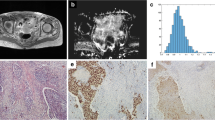

As treatment continued, the averaged ADC histogram gradually moved toward the right and turned into a more symmetrical shape with conspicuous descending peak (Fig. 2).

Dynamic changes of the averaged apparent diffusion coefficient (ADC) histogram and the corresponding histogram curve of 32 patients with advanced cervical cancers during concurrent chemo-radiotherapy (CCRT) (with a bin size of 50 × 10−6 mm2/s). a The averaged ADC histogram changes continuously during the course of CCRT. b The corresponding histogram curve gradually moves toward the right and turns into a more symmetrical shape with conspicuous descending peak as treatment continues. time point 1: before CCRT; time point 2: at the end of 2nd week of CCRT; time point 3: at the end of 4th week of CCRT; time point 4: immediately after CCRT completion